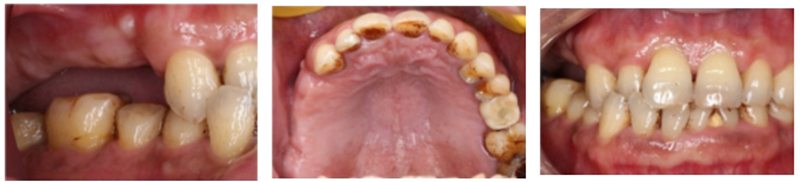

檢查:患者14、15、16、17缺失,無紅腫潰瘍,牙齦情況良好,口腔衛(wèi)生狀況良好。

診斷:14、15、16、17缺失

處理:通過數(shù)字化種植導航進行15、16、17種植修復

®該患者需連續(xù)種植三顆植體,手術難度高。需保證相鄰植體位置關系符合種植要求。徒手種植難以保證其位置一致性。

®主刀醫(yī)生經(jīng)驗豐富,通過石膏模型排牙確定咬合關系,放射阻射材料提前放入缺牙區(qū),確定CBCT中牙冠位置,擺放種植體。遵循修復引導種植原則。